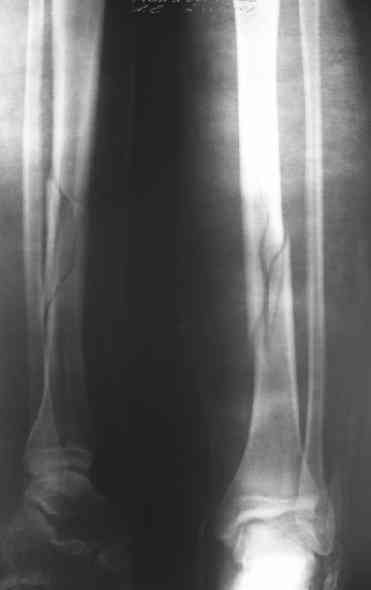

Вчера первый раз синтезировали голень гвоздем Fixion.

Спиральный оскольчатый перелом, ниже середины, у молодого парня. Сделали "классический" вариант гвоздя, который еще без винтов. Получилось все легко. Не торопясь, сделали операцию минут за 20. См. фото.

В отношении ранней нагрузки при спиральных переломах лучше не торопиться. По данному случаю необходимо достигнуть исчезновения щели между штифтом и внутреним кортексом по Rg. А так картинка прекрасная - и длина сегмента и репозиция. Можно поздравить, коллега!